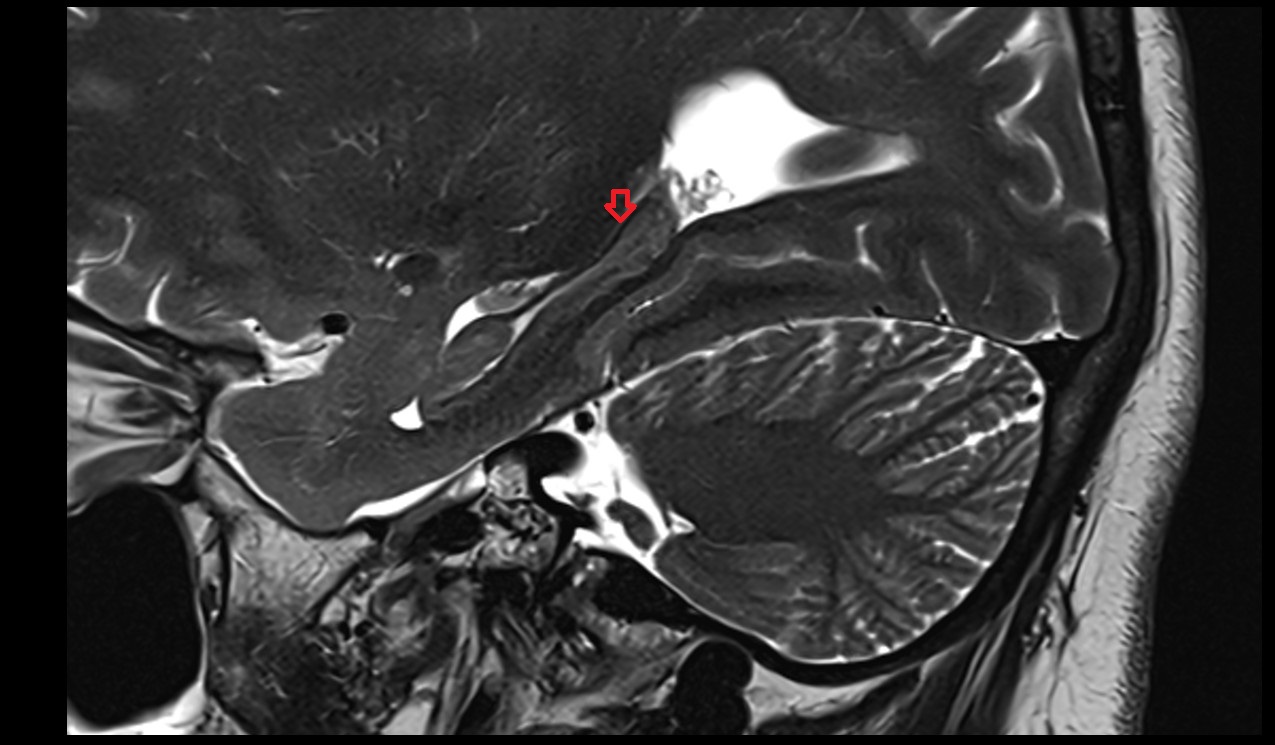

- Temporomandibular joint

- Articular disc of temporomandibular joint

- Articular eminence

- Mandibular condyle

- Mandibular fossa